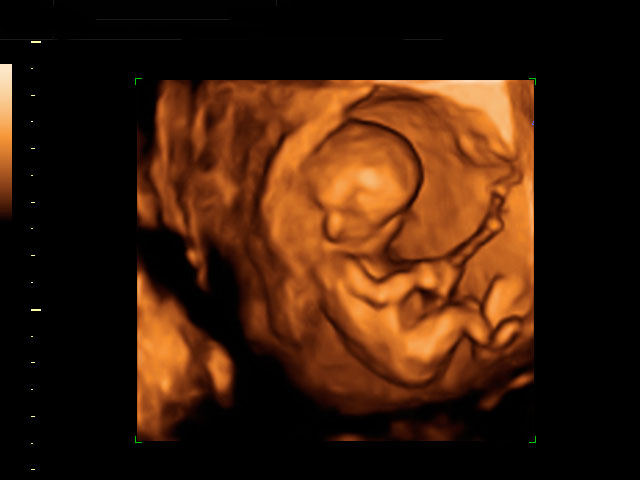

Ecografía 4D de la semana 12: Feto mirando "a la cámara"

Esta ecografía 4D muestra a un bebé de 12 semanas de gestación que se encuentra situado contra la pared del útero materno. El feto parece mirar varias veces hacia el ecógrafo y se tapa la cara con los brazos. Puede observarse con gran detalle la estructura ósea de la mano.

Ecografía en 4D de un feto de 12 semanas "mirando a la cámara"

A este niño de 12 semanas de gestación parece que le ha "pillado" el ecógrafo desprevenido y se quiere esconder. El bebé está contra la pared uterina: se da cuenta de que el ecografista le está "enfocando" y parece con si se quisiera esconder del público, como las estrellas de cine. Mira varias varias veces "a cámara", en una actitud sorprendente; se tapa la cara con los brazos. La mano se perfila perfectamente, así como muchas de sus estructuras óseas, mientras se esconde cara a la pared uterina.